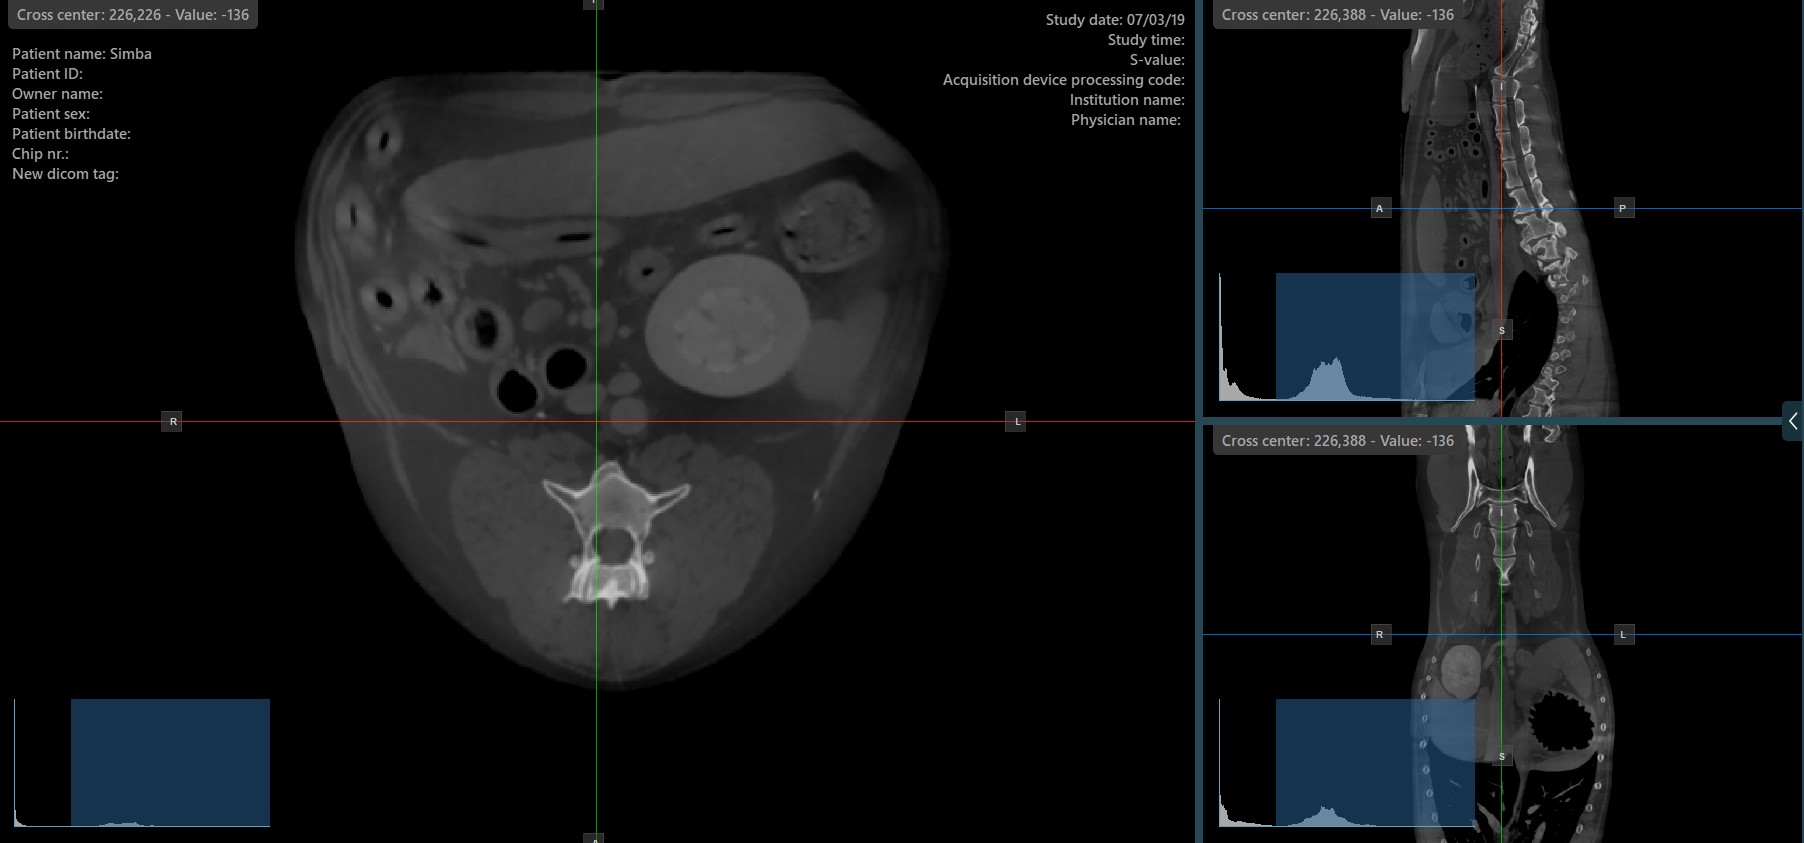

The slicers in MPR view show the intersections and orientation of the three image planes displayed in the active viewports. Users can modify the slicers and change the cross-sectional position of the slices based on the 3D volumetric data.

Each slicers is distinguished by their specific color, which representes the image plane:

The blue slicer marks the axial plane of the object (perpendicular to the ground)

The red slicer marks the coronal plane (parallel to the ground)

The green slicer marks the sagittal plane (perpendicular to the body)

Show/Hide Slicers¶

By default, the slicers are visible on the top of the images. The corresponding icon in the left toolbar of the CT Viewer will be selected when the slicers are visible.